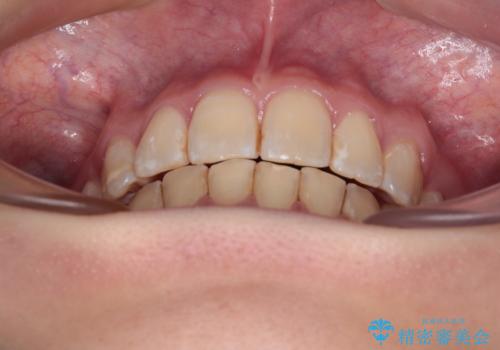

【モニター】出っ歯と八重歯 抜歯矯正でスッキリとした口元に

抜歯矯正により、口元の印象だけでなく、横顔の印象も大きく改善されました。